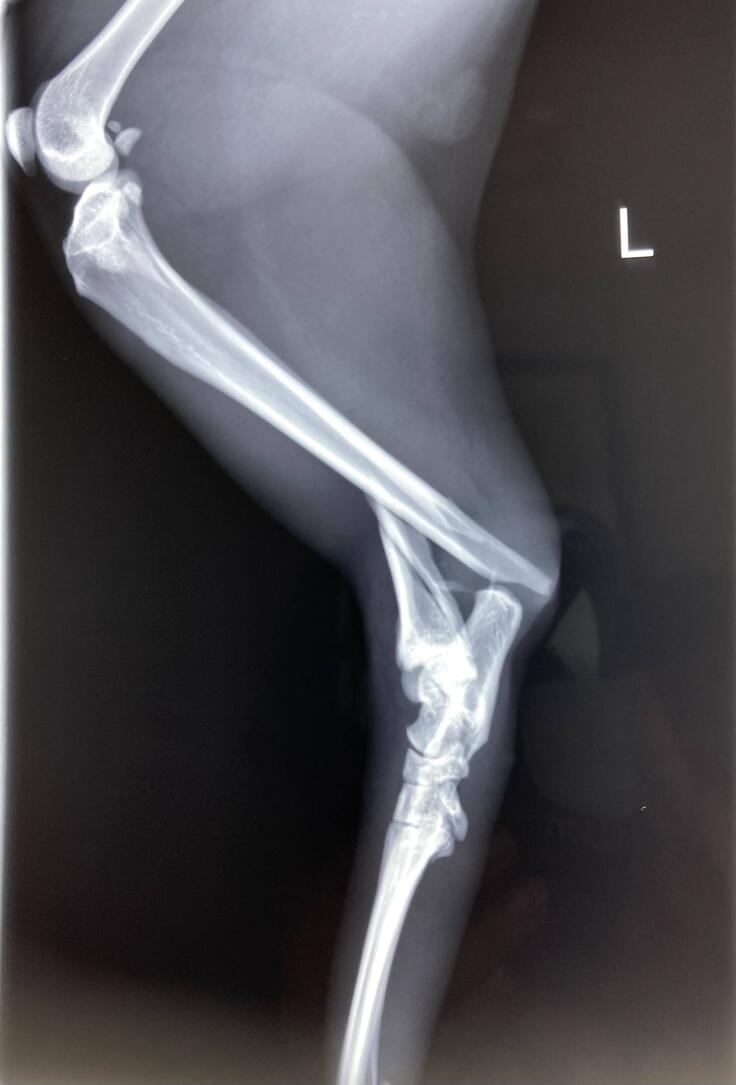

今回このくーちゃんが左後ろ足を開放性剝離骨折してしまいました。骨が3分割と小さな骨に分かれてしまっていてプレートを入れ小さい骨はピンで止めていただき手術は大成功しました。しかし創部に感染があった為術後も入院が長引きました。退院して2日後又発熱しぐったりし受診、感染からの熱か再入院。その退院の2日後にまた患部が凄く熱くぐったりし受診。今回は手術の部位が再度骨折してしまっていました。毎日ケージの中でほぼほぼ寝たきりであったのですが何故か再度骨折。かなり痛みもある様で可哀想に熱もでていました。私は死んでしまうのではと夜中に何度も見に行く日々が続きました。

悲しいことに手術してもらった所が再度骨折。

上が7月10日、下が15日 真ん中の小さい骨がずれてピンが横を向いてしまっています。

現在ケージで安静にしていますが創部の感染のため骨ができにくく今後も再手術、最悪の場合切断の可能性は否定できないとDrより説明を受けています。